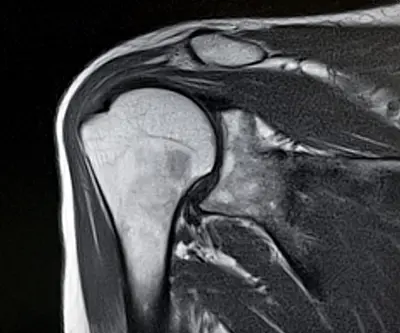

The shoulder is a ball and socket joint that allows a wide range of motion in the arm. It is formed by the head of the humerus (upper arm bone) and a part of the scapula (shoulder blade) called the glenoid. Between these bones lies a layer of cartilage called the labrum, which helps the bones glide smoothly against each other and provides stability to the joint.

Shoulder replacement surgery may be necessary when this joint becomes severely damaged or arthritic, causing significant pain, stiffness, or loss of function that interferes with daily activities.